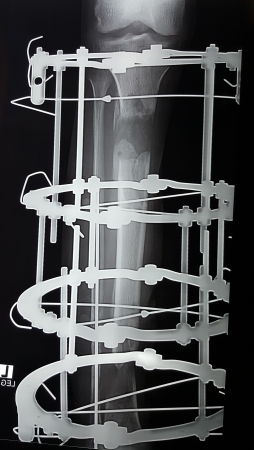

ইলিজারভ চিকিৎসা কি?

রাশিয়ায় ১৯৫০ সালে আবিষ্কৃত ইলিজারভ অর্থোপেডিক্স শাস্ত্রের একটি চিকিৎসা পদ্ধতি।

ইলিজারভ রিং/ ফ্রেইমটা কি?

এটি তৈরী হয় বিভিন্ন সাইজের ষ্টেইনলেস ষ্টিলের রিং, তার, রড-বোল্ট ও নাটের সংমিশ্রণে। ফ্রেইম গুলো নিখুতভাবে আকৃতি বিন্যাস করা হয় আলাদা আলাদা প্রয়োজন ও চাহিদা অনুযায়ী।

এই পদ্ধতিতে হাড় ধীরে ধীরে টানার ফলে রক্ত চলাচল বৃদ্ধি হয়ে নতুন হাড় তৈরি হয়। (Compression-distraction osteogenesis)